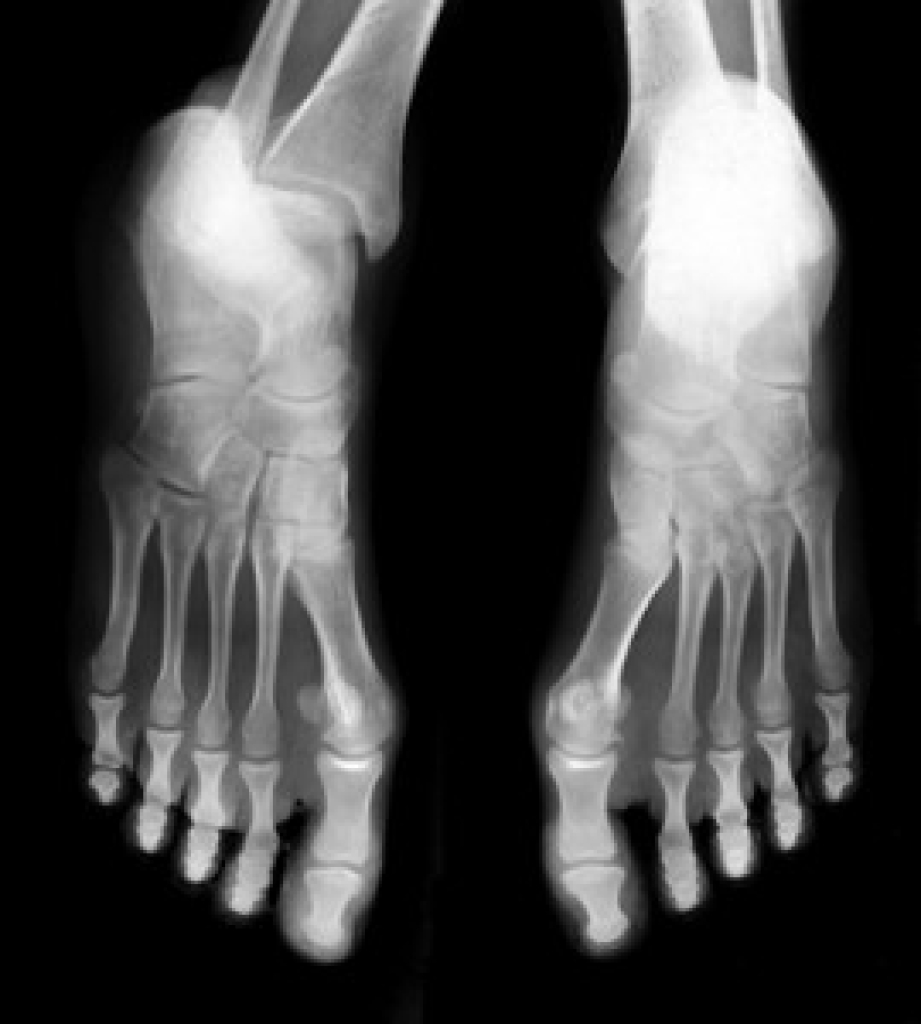

A broken foot can occur as a simple crack or as a complete break in the bone. Signs of a fractured foot can include tenderness, increased pain when standing or walking, numbness, swelling, bruising, trouble with movement, and an abnormal foot shape. If you believe that you have fractured your foot, you will likely need to visit a podiatrist for a proper diagnosis. In order to properly diagnose a foot fracture, an X-ray, CT scan, MRI or a bone scan will be necessary. Once a foot fracture is diagnosed, a cast, splint, or boot may be needed to limit the foot’s movement. A podiatrist will likely prescribe medicine, and in some cases surgery may be necessary as well.

Those that suspect they have a broken foot shoot seek urgent medical attention where a medical professional could diagnose the severity.